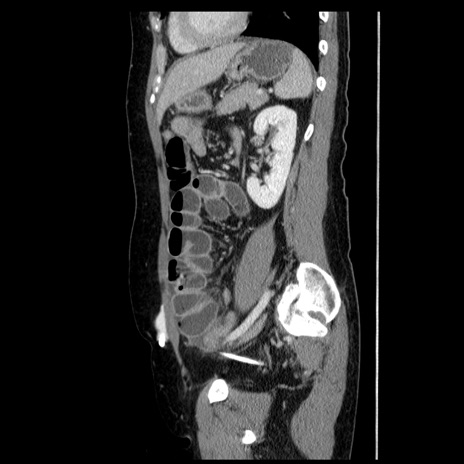

症例6(矢状断像)

横断像

【症例】50歳代女性

【主訴】下腹部痛

【現病歴】本日朝より下痢2回あり。 昼食を食べた後、嘔吐3回、下腹部痛認め、症状軽快せず、当院救急搬送。

最終食事:本日昼(生ものなし)。 昨日の夜、刺身を食ぺたとのこと。周囲に同様の症状の者なし。普段、排便は毎日あるとのこと。

【既往歴】卵巣癌術後(8年前に当院で卵巣摘出)

【身体所見】 意識清明、腹部:平坦、腸蠕動音→、やや硬、下腹部自発痛・圧痛あり、反跳痛あり、筋性防御なし。

【データ】WBC 16000、CRP 0.01